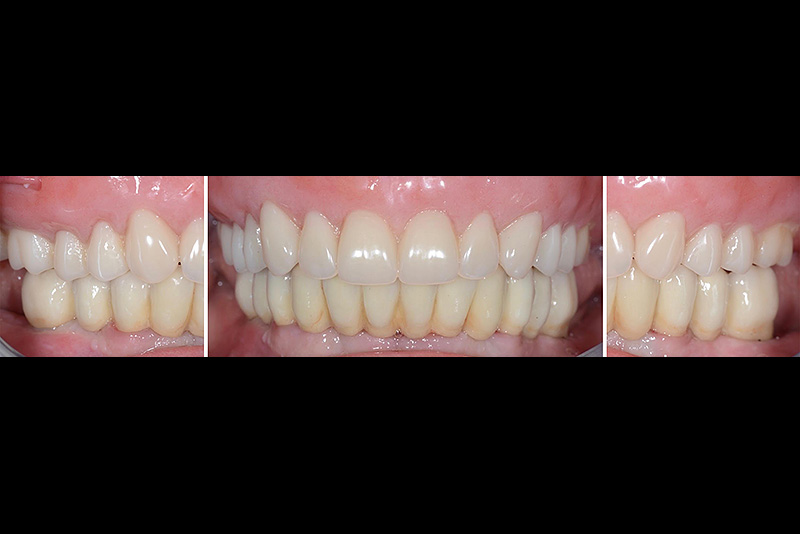

PREMESSA: in seguito all’estrazione dell’incisivo laterale superiore di destra, resasi necessaria per cause batteriche, si decide di affrontare il caso con il posizionamento di un impianto in sostituzione dell’elemento mancante dopo guarigione del sito infetto. Con tecniche rigenerative sia dei tessuti ossei mancanti a causa dell’infezione pregressa, sia dei tessuti gengivali che appaiono inizialmente troppo spostati in alto, si ripristina una corretta morfologia delle parabole (contorni) gengivali e delle papille interdentali (triangoli di gengiva tra due denti vicini).

Vengono utilizzati 2 tipi di provvisori: il primo, cementato ai denti vicini, viene utilizzato dal momento dell’estrazione del dente fino ad impianto osteointegrato (circa 6 mesi); il secondo, avvitato direttamente all’impianto, ha una funzione di prova estetica ma soprattutto di guida per la maturazione dei tessuti gengivali peri-implantari portandoli verso la maturazione completa prima di posizionare la corona finale in disilicato di litio.